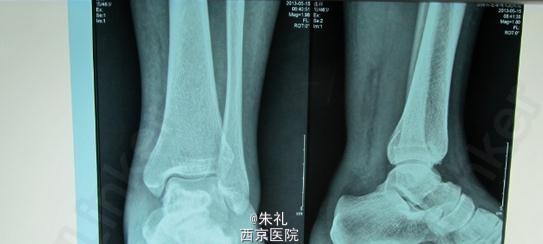

患者中年男性,因行走时拉伤致左下肢肿痛、活动障碍1月余,曾到当地性“消炎针输液”、当地行长期中草药外敷等治疗但效果不理想,到我院就诊,确诊为陈旧性跟腱断裂。

入院查体:左踝关节明显水肿,跟腱区可扪及一明显凹陷及空虚感,跟腱连续性中断,跖屈乏力 提踵试验(+),Thompson征(+),Matles试验(+)